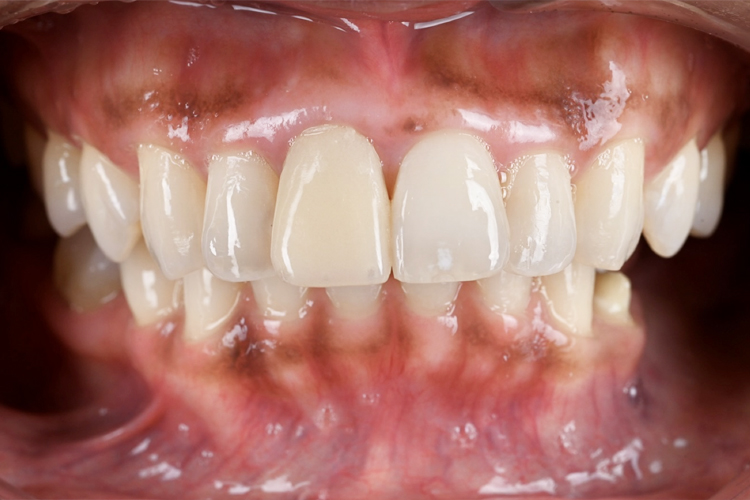

AFTER

左右非対称の改善と色調を自然な白さにすることで、全体的に馴染みました。

また、歯肉もガムピーリングを行ったことで健康的なピンクになり、さらに美しい仕上がりになりました。